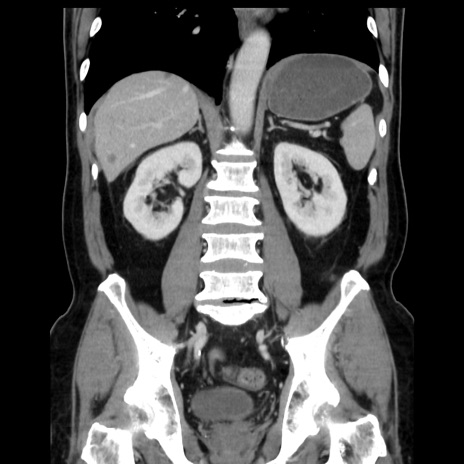

症例16(冠状断像)

【症例】 70歳代男性

【主訴】 腹痛、嘔吐

【現病歴】 約1ヶ月前より間欠的に腹痛と嘔吐あり、当院消化器内科を受診したところCTで多発する肝臓のLDAを指摘され、精査中であった。以降は消化器症状は安定していたが、2日前より嘔気と腹痛があり、同日より排便・排ガスが消失した。改善認めず、 本日、救急外来を受診した。

【既往歴】 大腸ポリープ切除後。

【身体所見】意識清明・会話良好、BT 36.3℃、BP 127/80mmHg、 P 80bpm、腹部:膨満あり、平坦・軟、上腹部正中および下腹部正中に圧痛あり、反跳痛なし、筋性防御なし。

【データ】WBC 7200、CRP 0.77